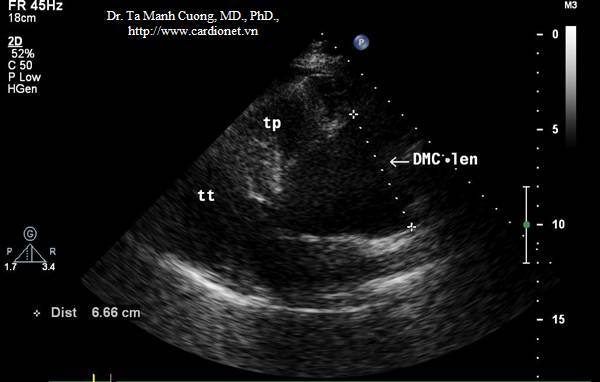

Phình động mạch chủ lên: ĐK 6.6 cm ở bn tách ĐMC týp A